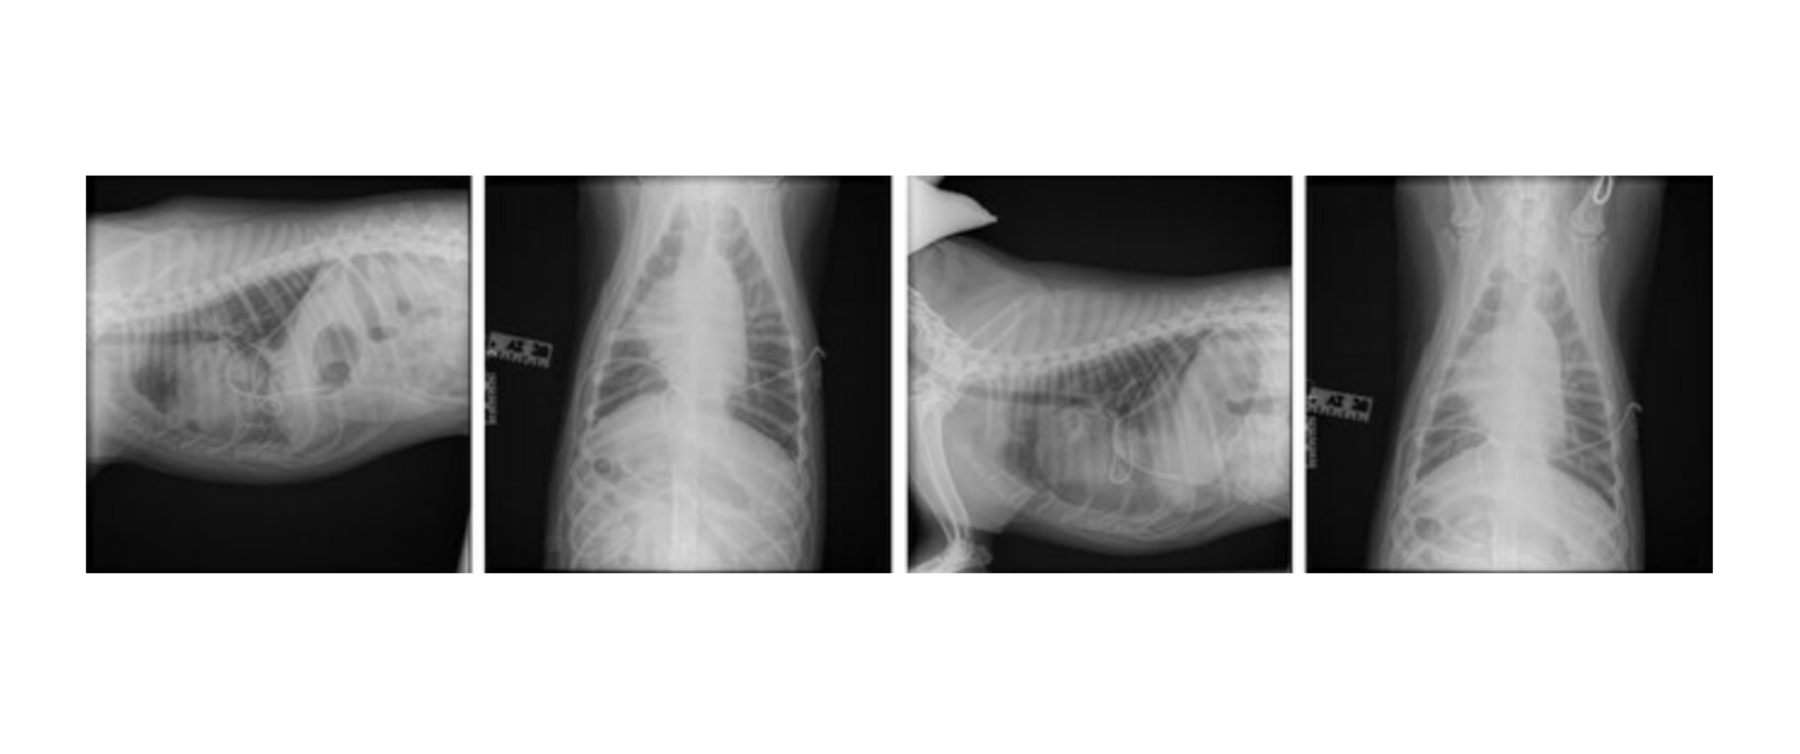

Radiographs (05-28-2024):

Findings: Mild residual pleural effusion, small amount of pleural air, presence of chest tubes

Interpretation: Post-chest tube placement with no primary intrathoracic lesions identified